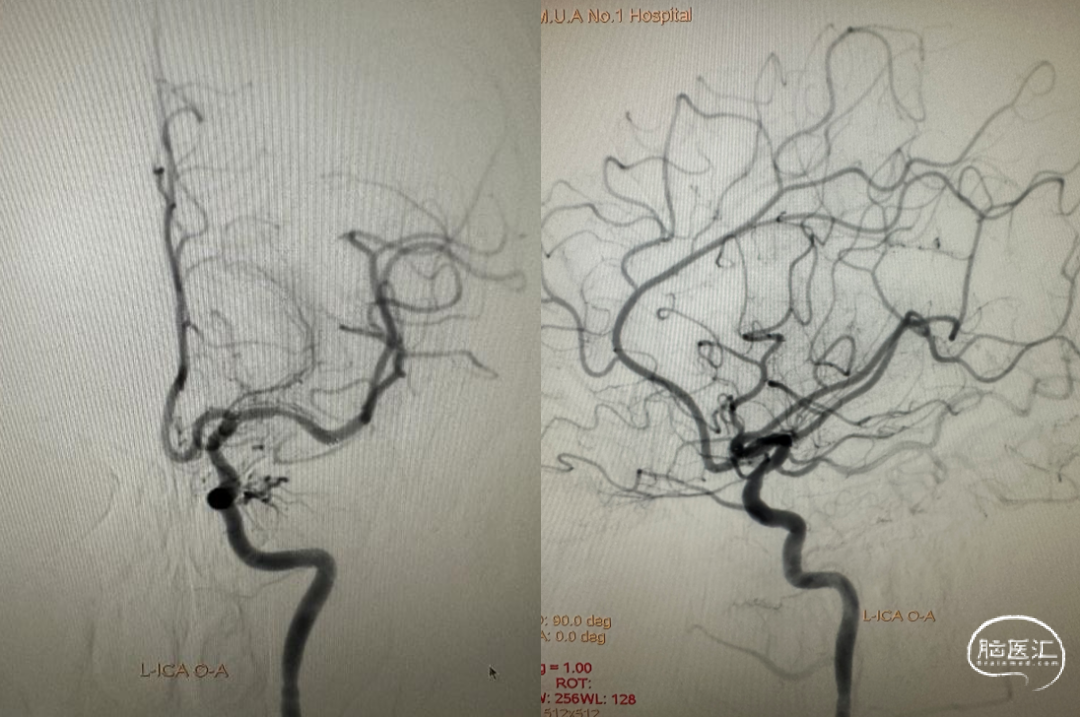

4.0*23mm 自膨式闭环支架沿21系列 Fastunnel®输送型球囊扩张导管输送到位造影。

支架释放后造影。

术后即刻影像及患者术后情况:

患者麻醉复苏后无神经功能障碍。患者术后标准正侧位造影。